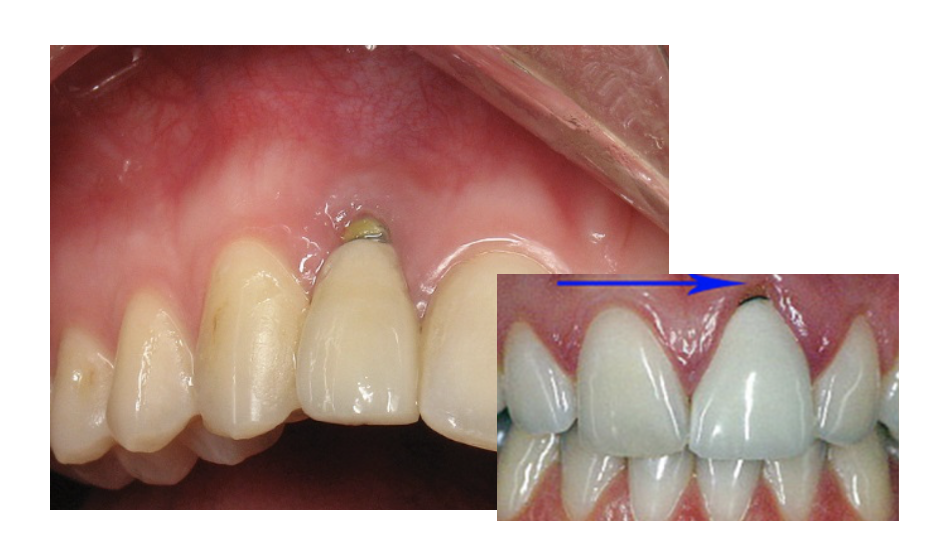

The next case was particularly challenging as the patient was congenitally missing tooth No. 10 and had an undersized lateral tooth No. 7. A different practitioner had placed an implant too high, presenting challenges with the gum. The patient declined tissue conditioning or training, adding to the difficulty of the case. The practitioner cemented a veneer and did a custom abutment, using a universal cement to bond to the enamel of No. 7 and to the titanium at No. 10. Cement offered easy cleanup and was radiopaque, allowing the practitioner to make sure no cement was left behind, which could cause peri-implantitis.

The girl in Figure 8 broke tooth No. 9 at school and came into the dental office with 30 minutes left in the workday. The practitioner did a zirconia crown on the tooth. Use of the universal allowed ease in material selection and cleanup, and good gingival health.